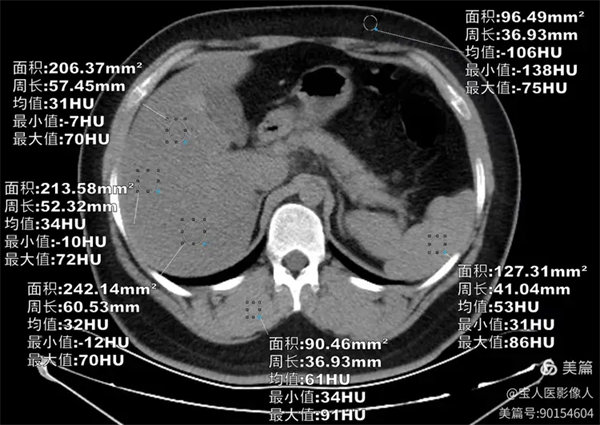

圖1

CT軸位,肝形態(tài),大小正常,CT值最低約31HU,較正常肝實質(zhì)密度降低。